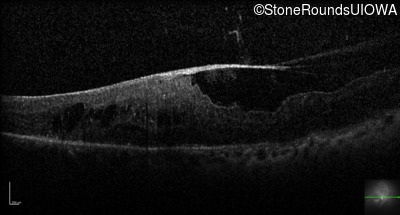

Optical Coherence Tomography - Right - 20/50 +2

Exemplar / OCT Stack

Optical Coherence Tomography - Left - 20/160